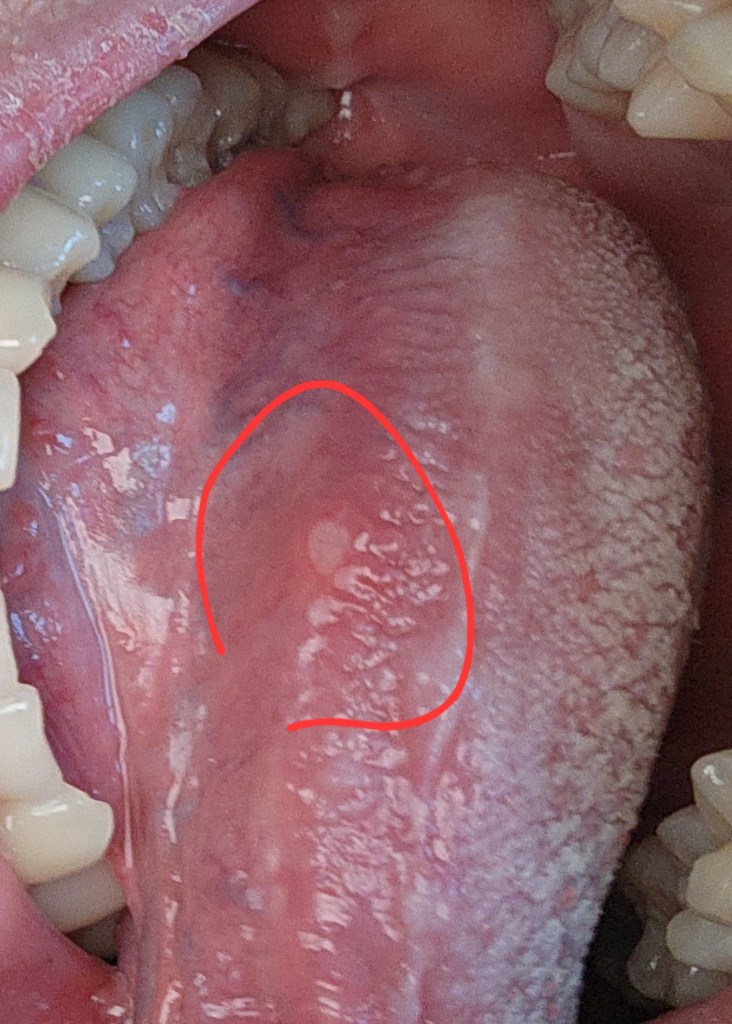

자주생기는 설염때문에 설암인지 무섭습니다(사진첨부)

사진에 보이는 것 처럼 설염(혀에 구내염)이 너무 자주생깁니다. 보통1주일 있으면 낫긴하는데 너무 자주생깁니다. 고등학생인데 설암가능성 높나요

구내염으로 보입니다. 반복적인 구내염은 설암보다는 자가면역질환이나 류마티스질환 등을 의심해볼수는 있습니다. 너무 자주 반복된다면 이비인후과를 한 번 방문해보시기 바랍니다.

현재 병변은 전형적으로 발생할 수 있는 구내염으로 보이며 설암의 가능성은 낮아보입니다.

• 아파타성 구내염이 호발하는 것 때문에 설암을 걱정하는 것은 과도한 걱정입니다. 만 19세에 피로함에 의해서 구내염이 호발하는 것은 종종 있을 수 있는 현상이며 설암의 가능성은 낮아보입니다.